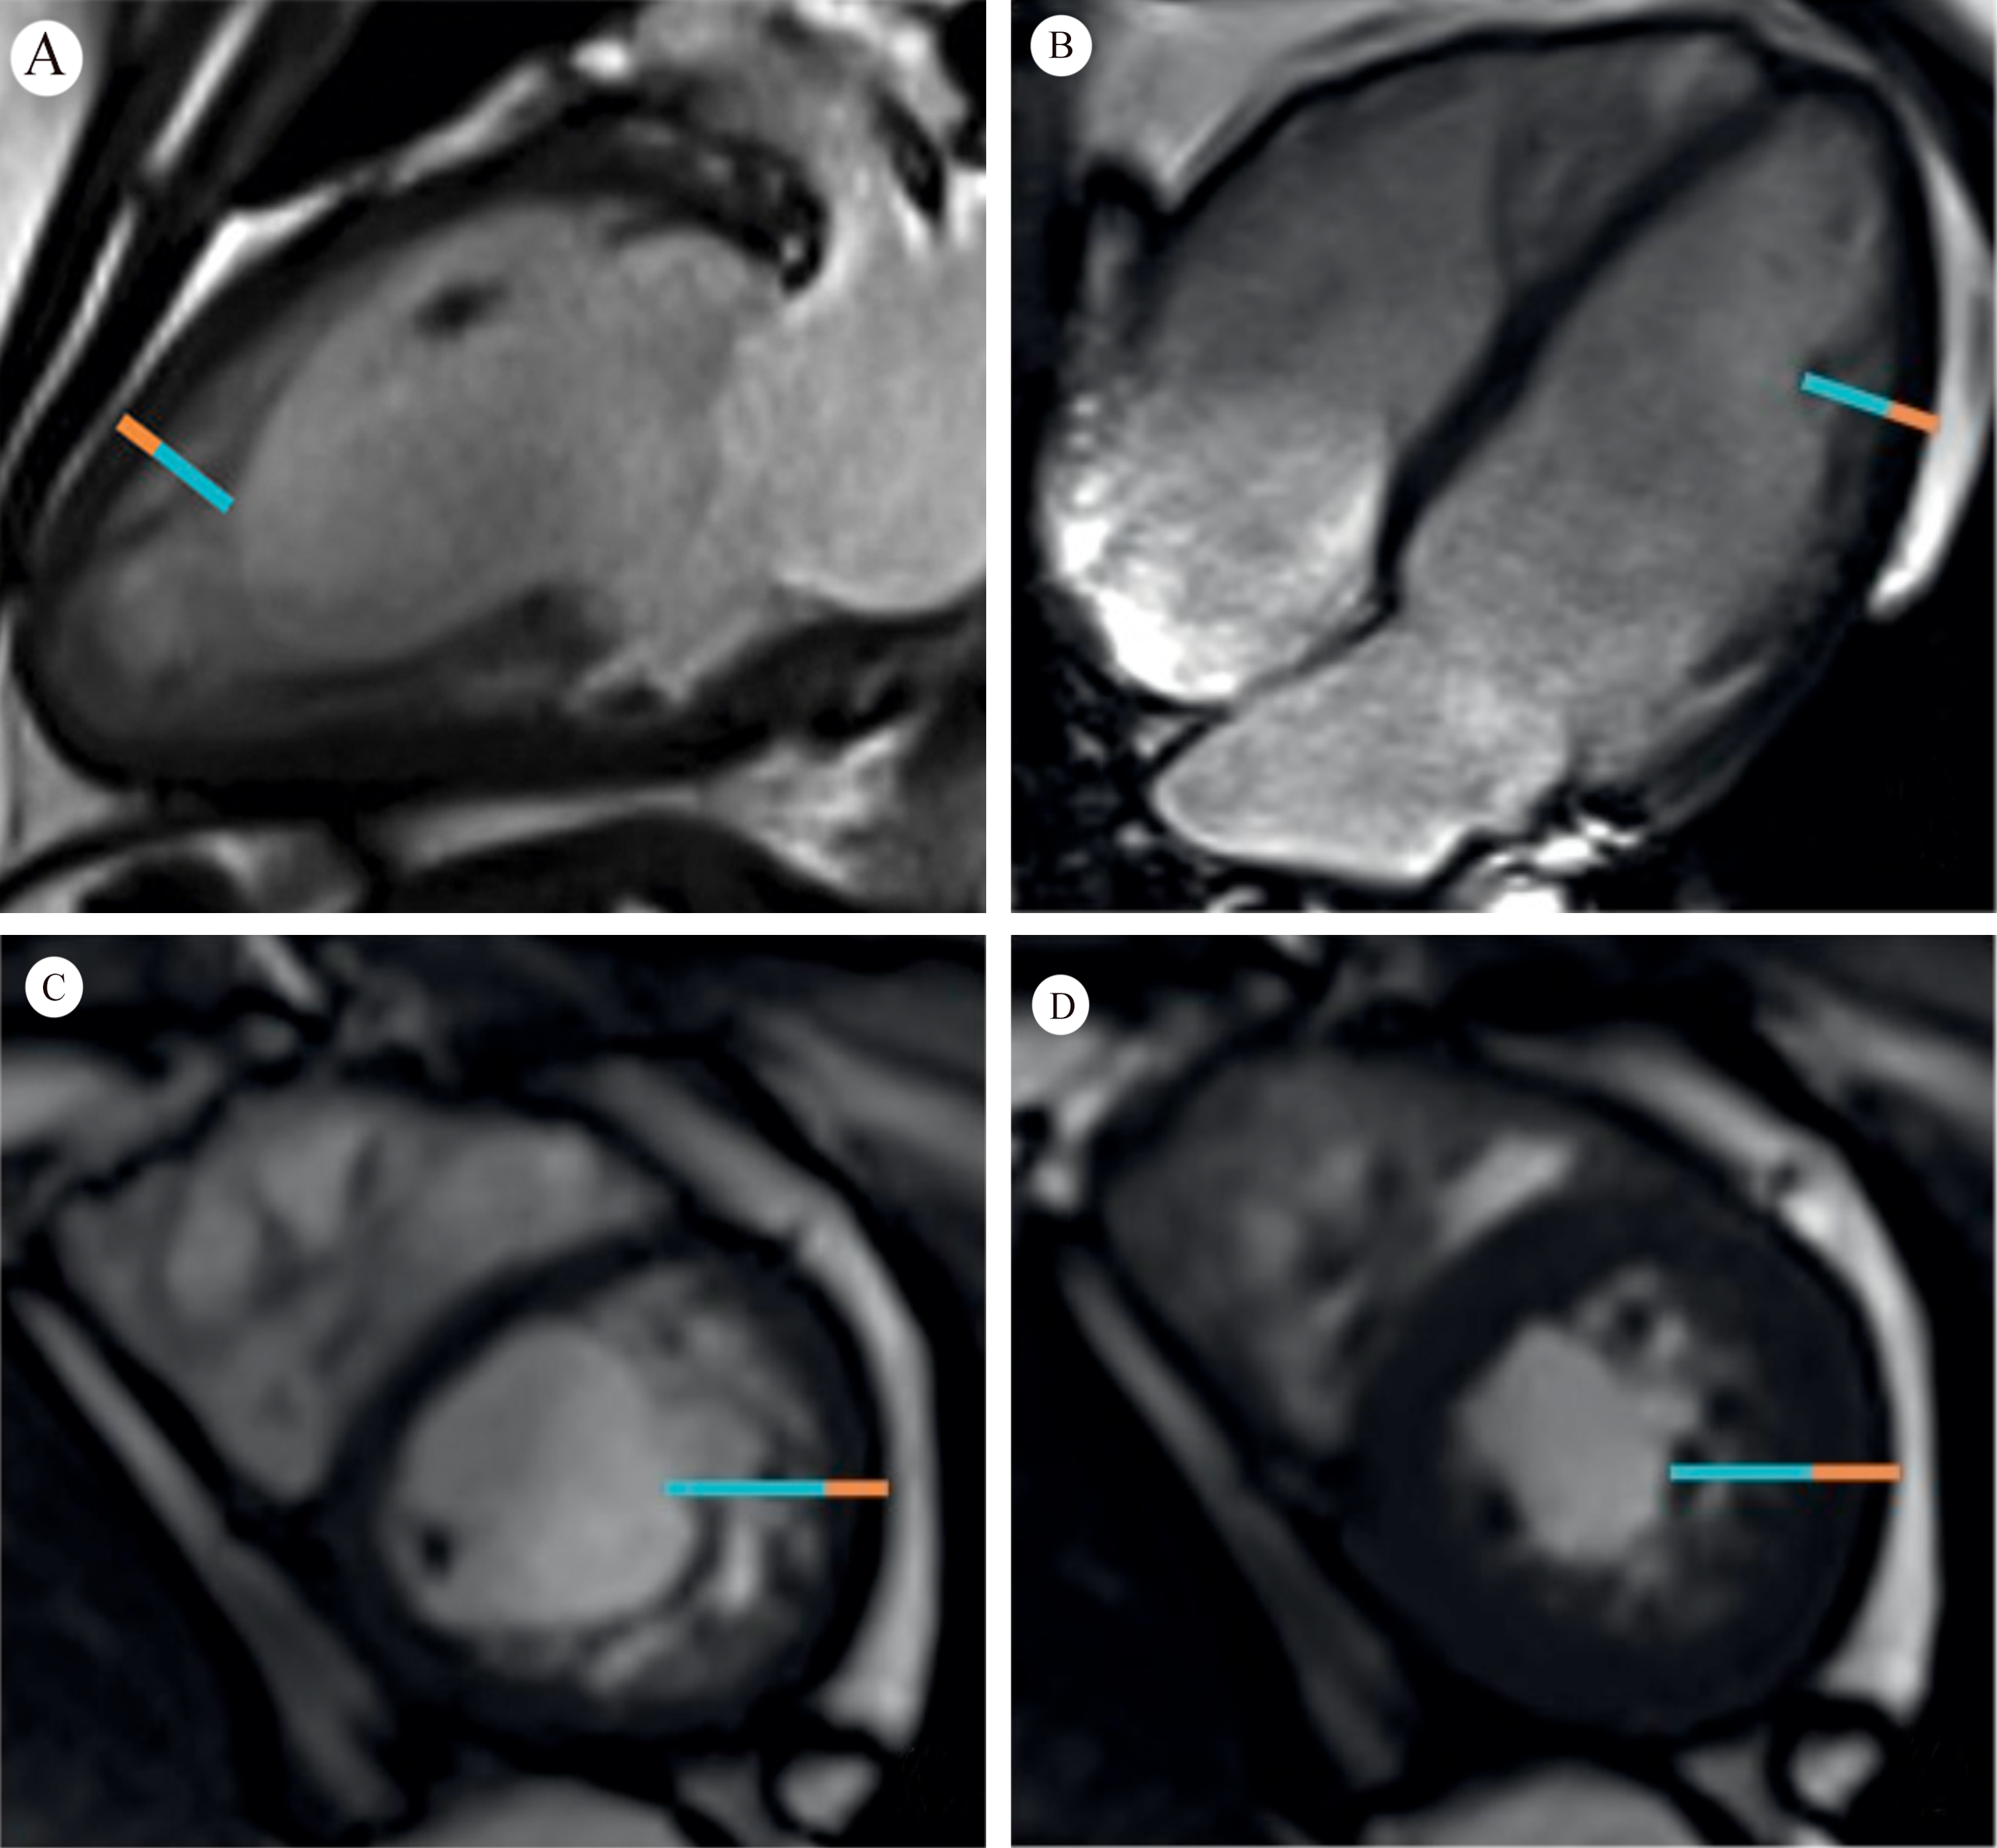

Saw-tooth cardiomyopathy (STC), first discovered in 2009 [1, 2], is a rare form of left ventricular cardiomyopathy, mainly affecting the apex and middle segment of the left ventricular wall and inferior wall. It may be evident in transthoracic echocardiography on admission. In most reported cases cardiac magnetic resonance (CMR) can provide a clearer view of the internal structure of the heart, with multiple dense myocardial protrusions similar to saw-tooth like crypts. These differ from left ventricular noncompaction (LVNC), which is characterized by noncompact myocardium in the layer of finely trabeculated myocardium adjacent to a layer of compacted myocardium [3]. The clinical course of STC ranges from asymptomatic to acute heart failure, and it can also be associated with a variety of cardiac complications. Typical images for STC are shown in Fig. 1 (Ref. [2]), and for LVNC in Fig. 2 (Ref. [3]) for comparison.

Fig. 1.Cardiac magnetic resonance (A and B); transthoracic echocardiography (C and D). Fig. 1A,B show numerous saw-tooth like muscular projections originating from the interventricular septum, some of them being tethered to the inferior LV wall. Fig. 1C,D show numerous saw-tooth like projections originating from the inferior interventricular septum to lateral LV wall (Fig. 1 is cited from Davlouros PA, et al. [2]).